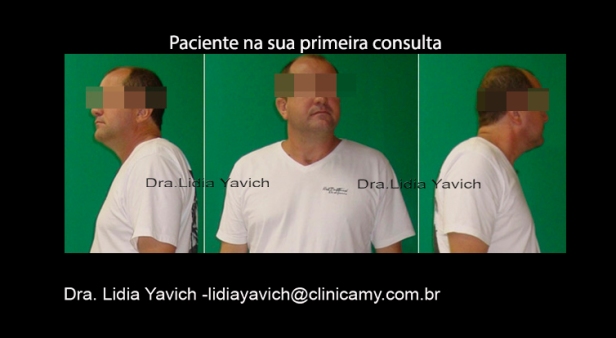

Comparação da imagem frontal do paciente: inicial e quatro meses após o uso do DIO. Notasse uma importante melhora no posicionamento da cabeça e ombros

Comparação da imagem do perfil direito do paciente: inicial e quatro meses após o uso do DIO. Notasse uma importante melhora no posicionamento da cabeça e ombros

Comparação da imagem do perfil esquerdo do paciente: inicial e quatro meses após o uso do DIO. Notasse uma importante melhora no posicionamento da cabeça e ombros

Comparação da imagem frontal do paciente: inicial, quatro e nove meses após o uso do DIO. O paciente teve uma recuperação na postura fisiológica.

Comparação da imagem do perfil direito do paciente: inicial quatro e nove meses após o uso do DIO. O paciente teve uma recuperação na postura fisiológica.

Comparação da imagem do perfil esquerdo do paciente: inicial,quatro e nove meses meses após o uso do DIO. O paciente teve uma recuperação na postura fisiológica.